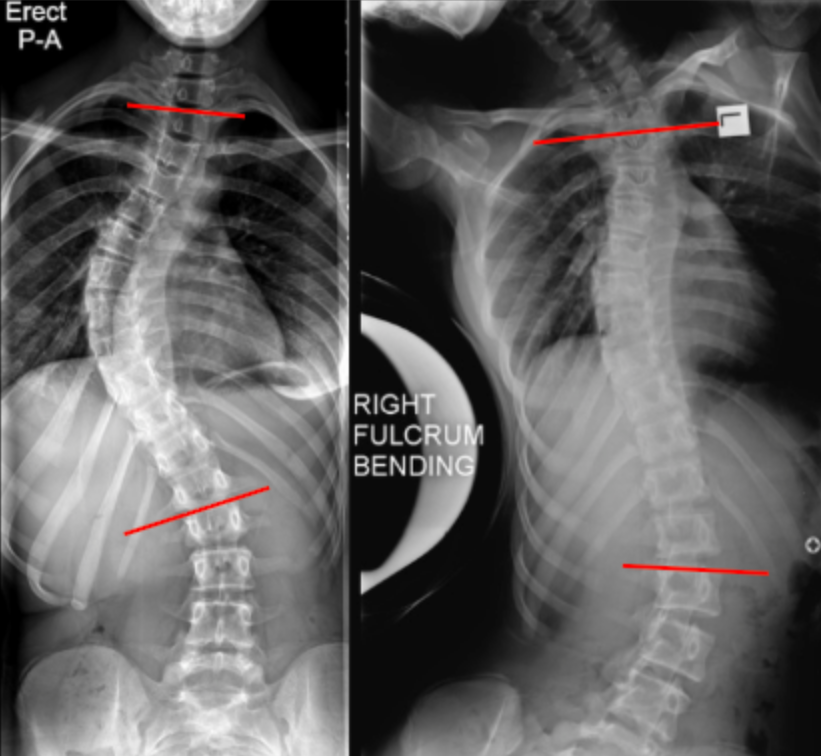

Traction and push-prone (fulcrum bending) films assess passive coronal plane flexibility of scoliotic curves by measuring the residual Cobb angle under externally applied corrective forces.

Unlike active side-bending films, these techniques minimize patient effort and better reflect the true mechanical stiffness of the curve, making them particularly useful for operative planning, implant selection, and prediction of postoperative correction.

• Measure the residual Cobb angle using the same end vertebrae as on the erect film.

Flexibility = (Erect Cobb - Traction / Push-Prone Cobb)/Erect Cobb* 100